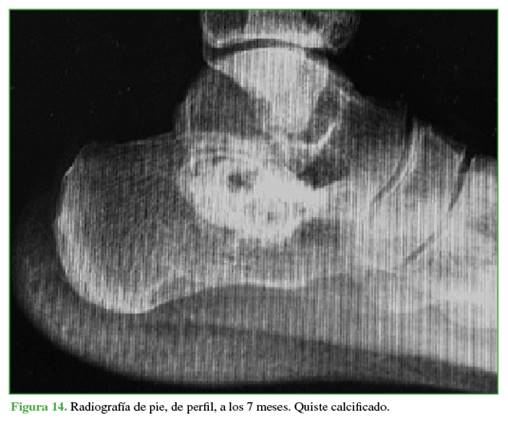

En los sucesivos controles clínicos y radiológicos, se comprobó la osificación de los quistes y la desaparición del dolor (Figuras 13-15). Después de más de 2 años de seguimiento, el paciente no ha vuelto a consultar. Como se sabe que el QOA puede recidivar, se debe mantener un control a más largo plazo.